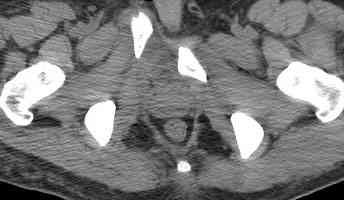

Уважаемые коллеги! опять вопрос по повреждению таза. Больной получил производственную травму 10 дней назад - удар балкой около 3 тонн в область верхней трети правого бедра и лона.

Был диагностирован перелом "типа бабочки" и повреждение уретры. Сделана цистостома. У насв отделении 3 дня. Имеется огромная флюктуирующая гематома с "галифе"-образной деформацией обеих бедер. Пнкционно эвакуировали в несколько приемов из подфасциальных полостей на бедрах около 3 литров геморрагического отделяемого с последующей эластической компрессией. При пункциях выявлено сообщение полостей на бедрах - видимо через поравннуюдиафрагму дна и полость таза - при удалении крови справа уменьшался объем левого бедра. Какой то активности проявялять покабоимся - аппаратная фиксация через отслоенные ткани представляется чреватой нагноением, открытая фиксация в условиях такой гематомы тоже не радует. Хотелось бы услышать ваше мнение

Типичная картина Morel-Lavallee повреждения.

Безуспешны многочисленные шприцевые эвакуации, мы лечим в операционной, доступом на латеральной поверхности, открытием образования с удалением и очисткой полости щеткой. Закрываем с дренажной трубкой (в архивах сайта) и накладывается мягкая повязка Спика из нескольких слоев эластичной повязки.

Следующим этапом через 5-6 дней приступаем к фиксацию повреждения таза, иначе прооперериванные на фоне Morel-Lavallee повреждения осложняются инфицированием послеоперационной раны.